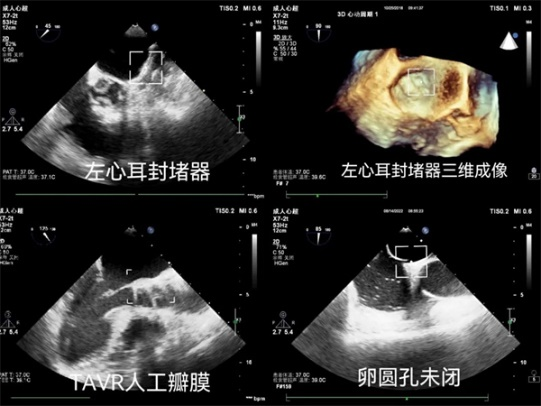

五、左心耳封堵术术前测量左心耳并排除血栓。